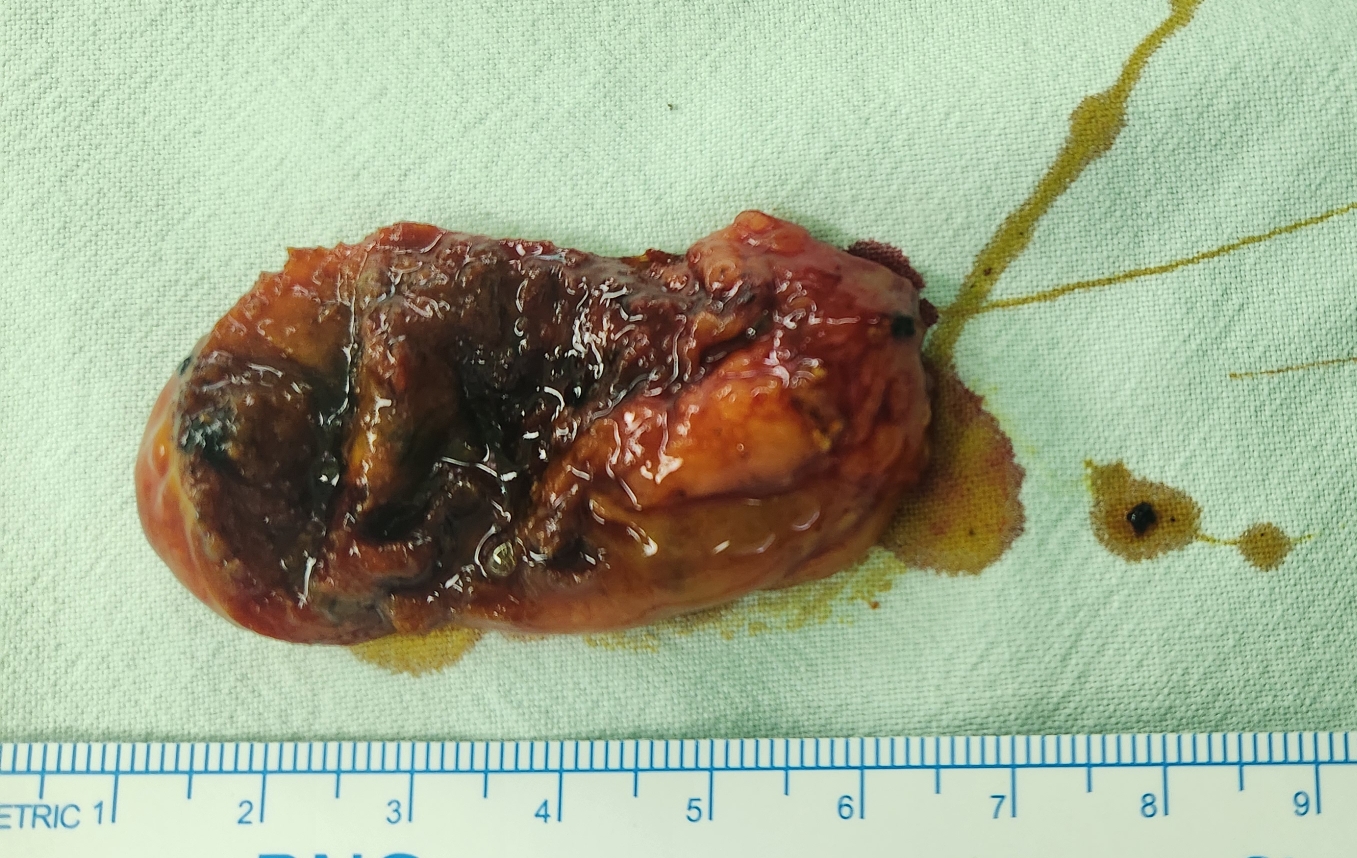

본원에서 검진 초음파 시행후 1.2cm의 담낭 용종이 발견되어 수술 위해 제 외래로 오셨던 분입니다.

방금 단일공 복강경 담낭절제술을 시행했습니다.

수술은 20분 걸렸습니다.